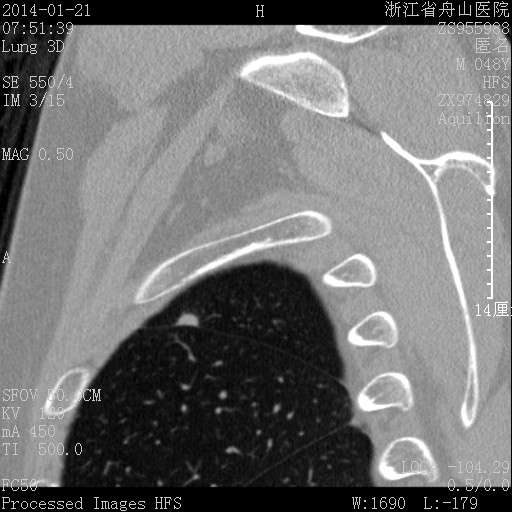

在脊柱旁 破坏力弱

收缩力弱,支气管血管完好。 再一例